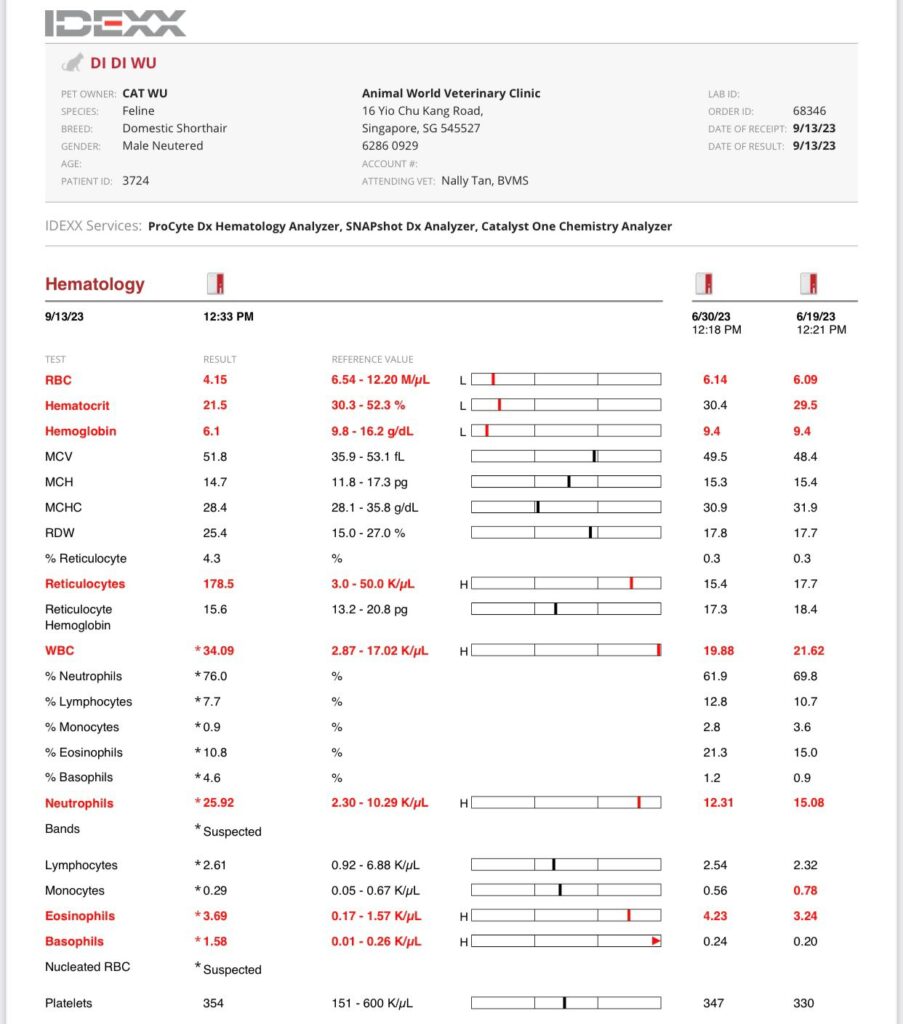

3.49kg – drop 180g in 4 days. V drastic weight change.

Got heart mur mur – taken probnp then

HR 240

Stomach so far ok.

Gum pale

To taken Cbc, Chem 15, lytes, probnp, pancreatitis.

Results: probnp normal. So mur mur due to anemic?

anemic for sure. HCT 21% plus I’ll start him on darbepoetin for sure too. Now is he needs ab? Waiting for dr nally to send summary.

I was worried about didi extreme high retic: “Re Didi – internal bleeding less likely as BUN is still normal and no black poo noticed? More of something else infectious/inflammation going on – mouth/nose/UTI?/pancreatits/neoplasia. The CREA was high end normal it may be higher as he is very skinny”

Cbc Chem10 done. His blood is soooo dark red. yet 29% only!?

HCT 29.2% – monitor le. Alt 216. Think ornipural working ok for him – continue, dr Brandon says that’s what he use last time like a supplement so no harm giving.

Cbc looks fine. Omg the price of Cbc so ex here. NEU EOS high, I’m happy actually – better than Low. Thought is like xiao Hui false alarm, can survive de!!! TP 10.5, glob 7.5. dr d didn’t mention he needs any ab at all.